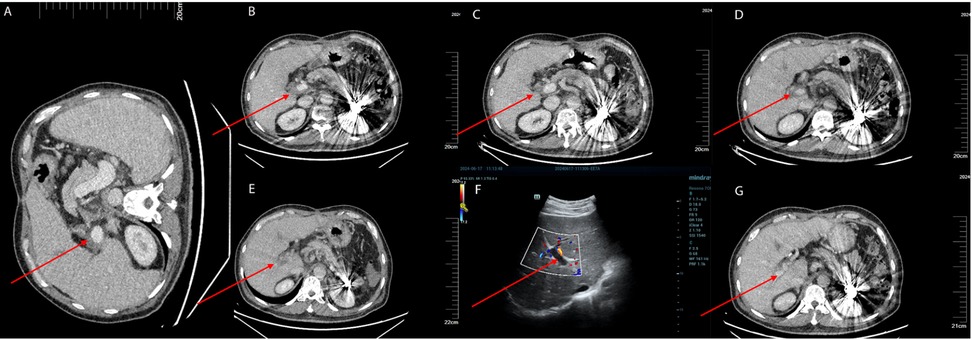

Despite initial improvements, the patient discontinued antiplatelet therapy (aspirin 100 mg daily and clopidogrel 75 mg daily) one month after surgery. Subsequent liver artery CTA revealed thrombosis (Figure 2B). On March 11, 2024, the patient was initiated on aspirin 100 mg daily and rivaroxaban 20 mg daily for anticoagulation. Follow-up CTA on April 2, 2024 demonstrated a reduction in thrombus size (Figure 2C).

Figure 2. (A) The patient underwent a follow-up enhanced abdominal CT scan on January 11, 2024, prior to splenectomy, which showed no thrombus in the portal vein. (B) The patient underwent an enhanced abdominal CT scan on March 11, 2024, with the red arrows indicating the location of the portal vein thrombosis. (C) The patient had a follow-up enhanced abdominal CT scan on April 2, 2024, which showed that the extent of the thrombosis had reduced compared to the previous scan. The red arrows indicate the location of the portal vein thrombosis. (D) The patient underwent a follow-up enhanced abdominal CT scan on June 3, 2024, which revealed a new thrombus in the right branch of the portal vein. The red arrows indicate the location of the portal vein thrombosis. (E) The patient had a follow-up enhanced abdominal CT scan on June 10, 2024, which showed an increase in the extent of the portal vein thrombosis compared to the previous scan. The red arrows indicate the location of the portal vein thrombosis. (F) The patient underwent a follow-up liver Doppler ultrasound on June 17, 2024, which still showed the presence of a portal vein thrombosis. The thrombus had not completely occluded the portal vein. The red arrows indicate the location of the portal vein thrombosis. (G) The patient underwent a follow-up enhanced abdominal CT scan on June 30, 2024, which demonstrated a decrease in the size of the portal vein thrombus compared to the previous scan. The red arrows indicate the location of the portal vein thrombosis.

Further complications and treatment

Due to the extraction of an inflamed wisdom tooth, the patient's medication was changed to rivaroxaban 10 mg once daily and aspirin was discontinued. On May 8, 2024, a PVT was detected through ultrasound in local hospital. The anticoagulation regimen was adjusted to aspirin 100 mg once daily and rivaroxaban 20 mg once daily. On June 3, 2024, a follow-up CTA revealed a new small thrombus in the right branch of the portal vein (Figure 2D). Intravenous infusion of heparin sodium was initiated while oral anticoagulants were ceased. A subsequent CTA on June 10, 2024 demonstrated an expansion of the thrombus (Figure 2E). Because the patient had previously undergone multiple splenic artery embolization procedures, he refused further interventional treatment at this stage. Therefore, peripheral vein infusion of urokinase was selected as the alternative approach. On June 13, 2024, peripheral infusion of urokinase (1.2 million units per 24 h) commenced along with aspirin at a dose of 100 mg once daily and rivaroxaban at a dose of 20 mg once daily.

The patient presented with gingival bleeding and hematuria, leading to a reduction in urokinase dosage to 1.8 million units per 24 h. On June 17, 2024, liver ultrasound revealed significant improvement in portal vein thrombosis (Figure 2F). Urokinase infusion was discontinued on June 19, 2024.

Outcome

A CTA on June 30, 2024 confirmed a decrease in thrombus size, indicating successful treatment (Figure 2G). The patient was discharged with continued oral administration of aspirin at a dose of 100 mg daily and rivaroxaban at a dose of 20 mg daily.